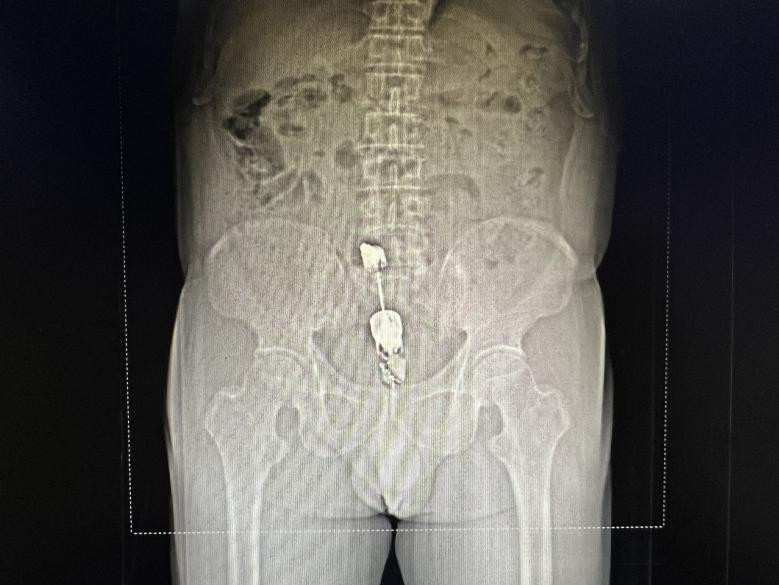

福建中醫(yī)藥大學(xué)附屬人民醫(yī)院急診科醫(yī)護(hù)接到電話后立即出診,將鄒老漢接回院治療。急診外科游杰醫(yī)生立即完善查體,發(fā)現(xiàn)棒狀物已完全沒(méi)入鄒老漢肛門(mén),又陪同其行腹部CT檢查后發(fā)現(xiàn)其尾部距離肛緣5cm。鄒老漢下腹墜脹難忍,大汗淋漓,十分擔(dān)心異物難以取出。為盡快取出異物,游杰醫(yī)生聯(lián)系肛腸科謝亞朦醫(yī)生進(jìn)行急診手術(shù)。終于在當(dāng)日凌晨手術(shù)成功取出了鄒老漢的體內(nèi)異物,手術(shù)順利,安返病房。鄒老漢于術(shù)后兩天,未發(fā)現(xiàn)并發(fā)癥,已平安出院。

CT發(fā)現(xiàn)體內(nèi)異物